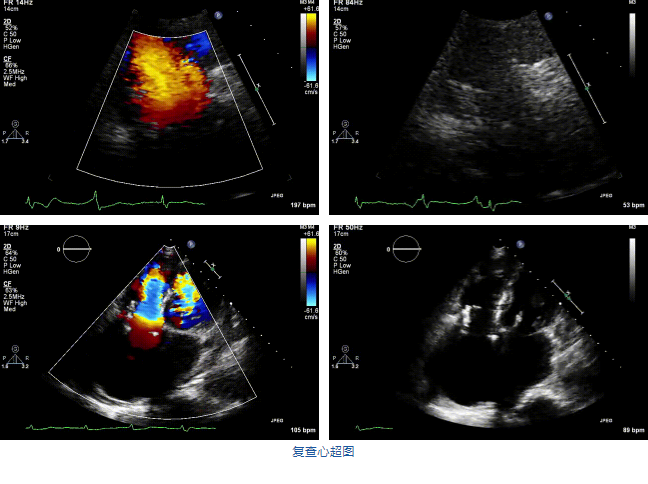

結(jié)合術(shù)前CT評(píng)估結(jié)果,葛均波院士團(tuán)隊(duì)最終決定選用LuX-Valve Plus 50mm和55mm兩種型號(hào)的瓣膜,并于2021年11月30日順利完成LuX-Valve Plus經(jīng)血管三尖瓣置換術(shù),手術(shù)室即刻拔除氣管插管,術(shù)后第二天轉(zhuǎn)出心內(nèi)科監(jiān)護(hù)室,下床活動(dòng)。術(shù)后患者三尖瓣反流癥狀得到顯著改善,復(fù)查心超結(jié)果顯示人工三尖瓣瓣膜支架固定穩(wěn)定,瓣葉關(guān)閉形態(tài)未見(jiàn)異常,未見(jiàn)明顯反流。